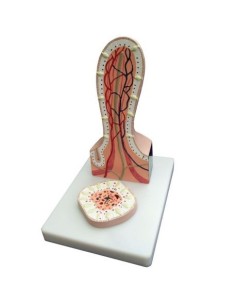

Dal cranio in 22 parti con incastri magnetici ai modelli di colonna vertebrale, da quelli di articolazioni a quelli di cuore, ogni pezzo della nostra collezione è progettato per un’immersione totale nello studio dell’anatomia umana. I nostri modelli, realizzati tramite scansioni di ossa vere, garantiscono un’esperienza tattile autentica e una fedeltà di peso quasi identica agli originali.

Essenziali per studenti e professionisti, i nostri modelli anatomici sono strumenti didattici che permettono di osservare le strutture anatomiche con precisione, eliminando la necessità di dissezioni o studi invasivi. Sono inoltre utili per spiegare ai pazienti le patologie, rendendo la comunicazione più efficace e risparmiando tempo prezioso.